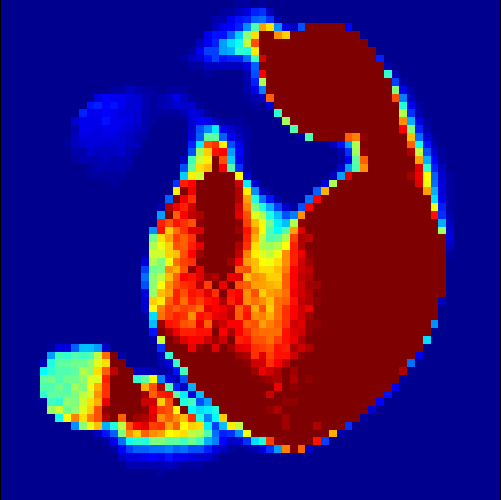

The first data set consists of a heart-shaped region and three circles on a static background (see figure 1 (a)). The two smaller circles are assumed to belong to

the same tissue type and therefore to the same subregion, which causes a total of four subregions, including the background. To simulate a more realistic application of dynamic SPECT

imaging, we used a synthesized representation of a rat liver as a second data set (see figure 1 (b)). The temporal concentration curves used to simulate the data sets

are shown in figure 2. As before, the total number of subregions was chosen to be equal to four in order to provide a both simple and realistic shape model.

In a first test, every image sequence was reconstructed out of the exact given sinograms. Additionally we tested noise corrupted data by first scaling the sinogram by a parameter , corrupting them with Poisson noise via the MATLAB imaging toolbox command imnoise and finally rescaling the image to the original range (see figure 4). The average count number per time step (i.e. the average of the discrete -norm of the data at each time step) is approximately in case of the heart-shaped data set and ca. in case of the rat liver simulation. The results at a certain number of time steps can be seen in figure 6 and 7. For comparison, we additionally performed a reconstruction with a simple alternating EM method, keeping the assumption that the tracer can be modelled as a sum of indicator functions and subconcentration curves, but neglecting any regularization terms. In all tests, the outer iteration number was set to 1000 with 10000 inner iterations per subproblem, to obtain a result within a reasonable time period. As stopping criterion, we chose the primal dual residual (cp. [12]) for the inner and the maximum over the Frobenius norms of and for the outer iterations. The results are displayed in 6 and 7 respectively.

As one can see in both figures, the reconstruction method applied to each data set performs very well, especially in contrast to the simple alternating EM method. This clearly shows the benefits of the proposed regularization methods. In case of noise-free given data, the shape of every object, where especially the heart is of higher interest, is clearly defined. As expected, we often observe errors in the edges of each region and where two regions are directly connected (the heart and the upper left circle). This causes the algorithm to incorrectly assign these pixels to another region. Furthermore, the reconstruction difficulties increase with an increase in noise. Some more pixels are assigned to the wrong region, which leads to a small hole-like structure within the heart region and causes a slight blurring effect. In the second data set the method clearly outperforms several other approaches by providing very clearly defined regions and even reconstructing fine structures of the phantom. However, as mentioned before, a clear reconstruction of the rat liver required highly optimized parameter sets, which makes the whole problem quite susceptible to parameter changes.